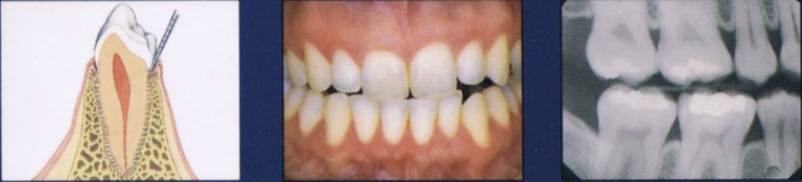

Describe the health stage

Firm and resilient tissue, minimal sulcus depth

Coral pink

Variations in color may depend on race

Evidence of previous disease may be present